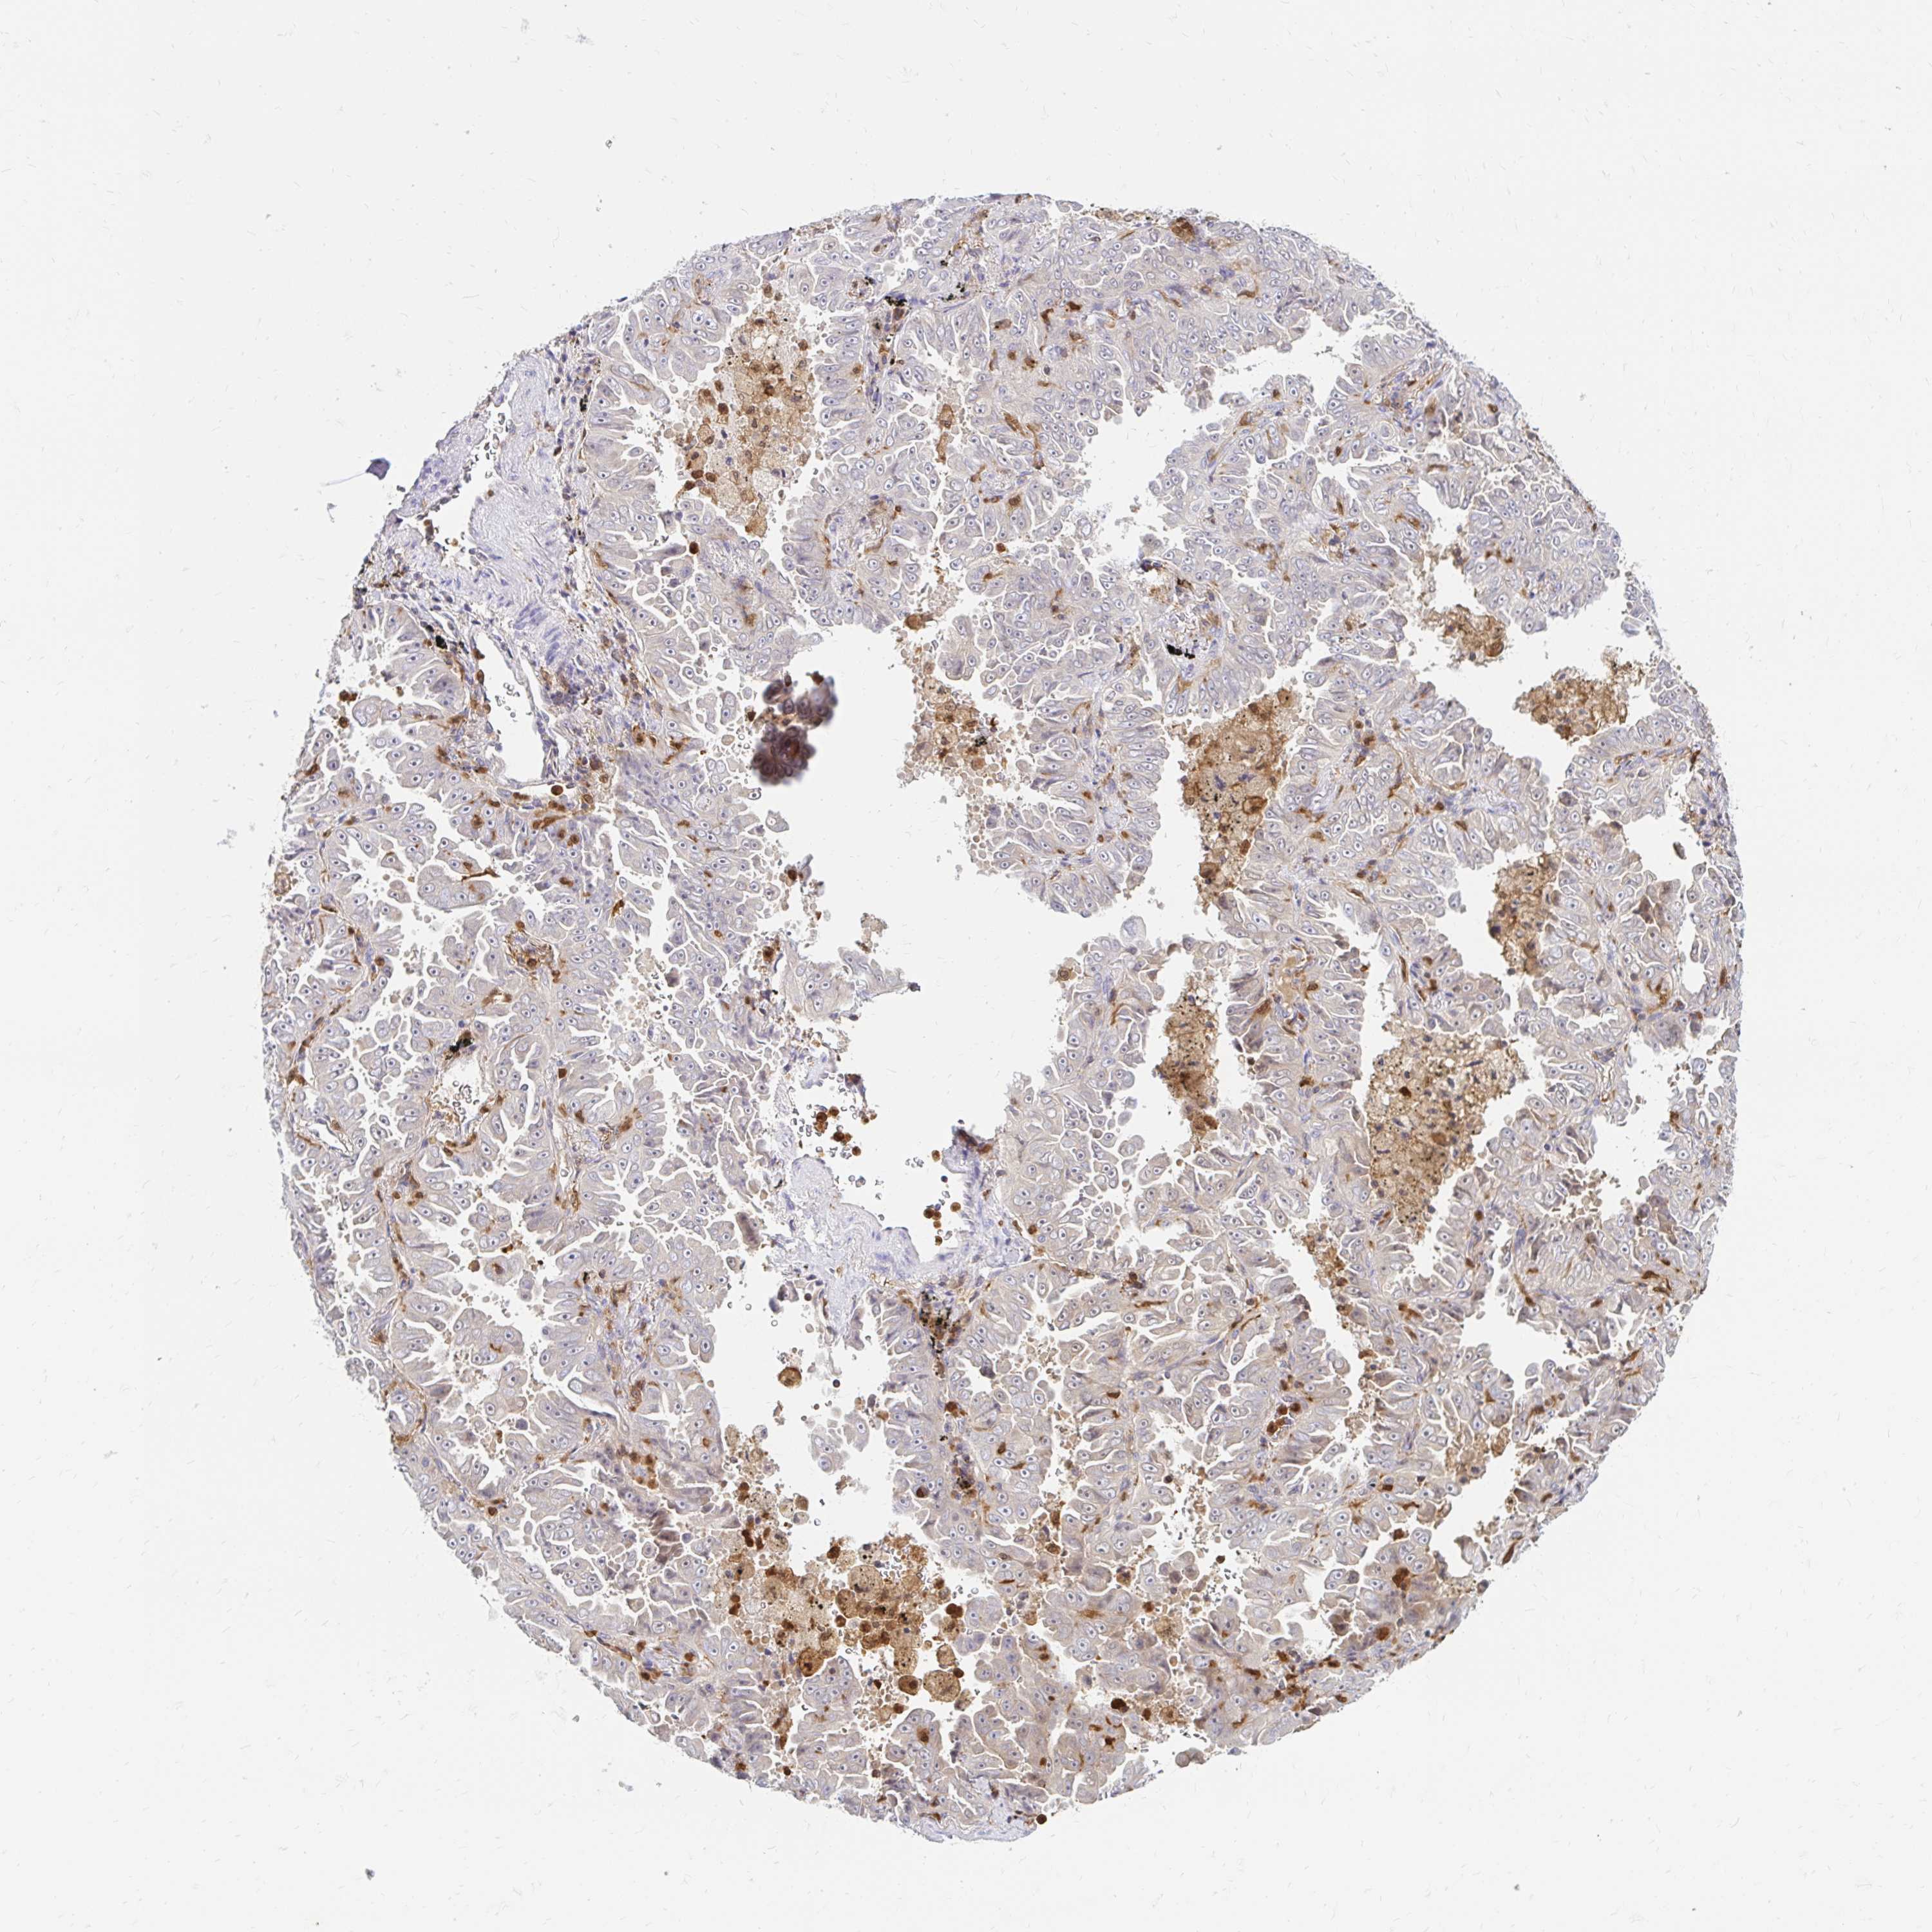

LUNG ADENOCARCINOMA (TCGA) - Interactive survival scatter ploti

The Survival Scatter plot shows the clinical status (i.e. dead or alive) for all individuals in the patient cohort, based on the same data that underlies the corresponding Kaplan-Meier plots. Patients that are alive at last time for follow-up are shown in blue and patients who have died during the study are shown in red.

The x-axis shows the expression levels (FPKM) of the investigated gene in the tumor tissue at the time of diagnosis. The y-axis shows the follow-up time after diagnosis (years). Both axes are complimented with kernel density curves demonstrating the data density over the axes. The top density plot shows the expression levels (FPKM) distribution among dead (red) and alive patients (blue). The right density plot shows the data density of the survived years of dead patients with high and low expression levels respectively, stratified using the cutoff indicated by the vertical dashed line through the Survival Scatter plot. This cutoff is automatically defined based on the FPKM cutoff that minimizes the p-score. The cutoff can be changed by dragging the vertical line or by entering a cutoff value in the square labeled "Current cut-off".

Under the Survival Scatter plot the p-score landscape (black curve; left axis) is shown together with dead median separation (red curve; right axis). Dead median separation is the difference in median mRNA expression between patients who have died with high and low expression, respectively. It is calculated as follows: median FPKM expression of dead patients with high expression - median FPKM expression of dead patients with low expression. This is intended to aid the user in visually exploring custom cutoffs and the associated p-scores and dead median separation.

Individual patient data is displayed and can be filtered by clicking on one or more of the category buttons on the top of the page. Categories describing expression level and patient information include: high, low, alive, dead, female, male and tumor stages. The scale of the x-axis can be toggled between linear and log-scale by clicking on the "x log" button. Mouse-over function shows TCGA ID, patient information and mRNA expression (FPKM) for each patient.

& Survival analysisi

Kaplan-Meier plots summarize results from analysis of correlation between mRNA expression level and patient survival. Patients were divided based on level of expression into one of the two groups "low" (under cut off) or "high" (over cut off). X-axis shows time for survival (years) and y-axis shows the probability of survival, where 1.0 corresponds to 100 percent.

PYCARD is not prognostic in Lung Adenocarcinoma (TCGA)

: 72.91